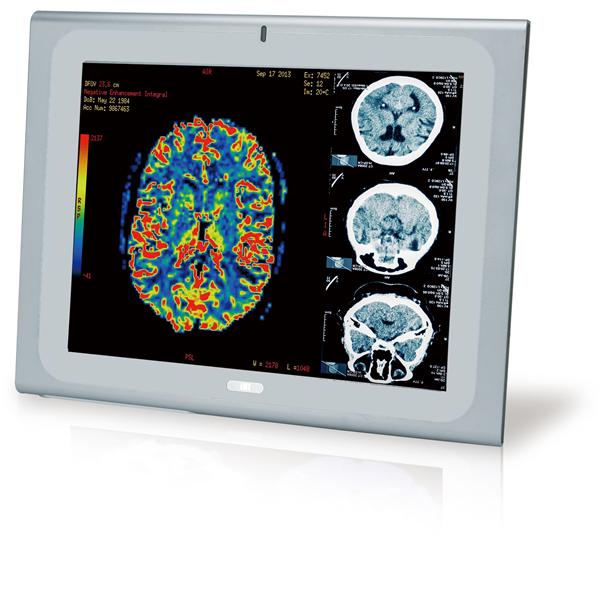

IEI Technology | Panel PCs 17" Medical Pan... |

IEI Technology | Panel PCs 19" Medical Pan... |

IEI Technology | Panel PCs 17" Medical Pan... |

IEI Technology | Panel PCs 19" Medical Pan... |

IEI Technology | Panel PCs 17" Medical Pan... |

IEI Technology | Panel PCs 19" Medical Pan... |